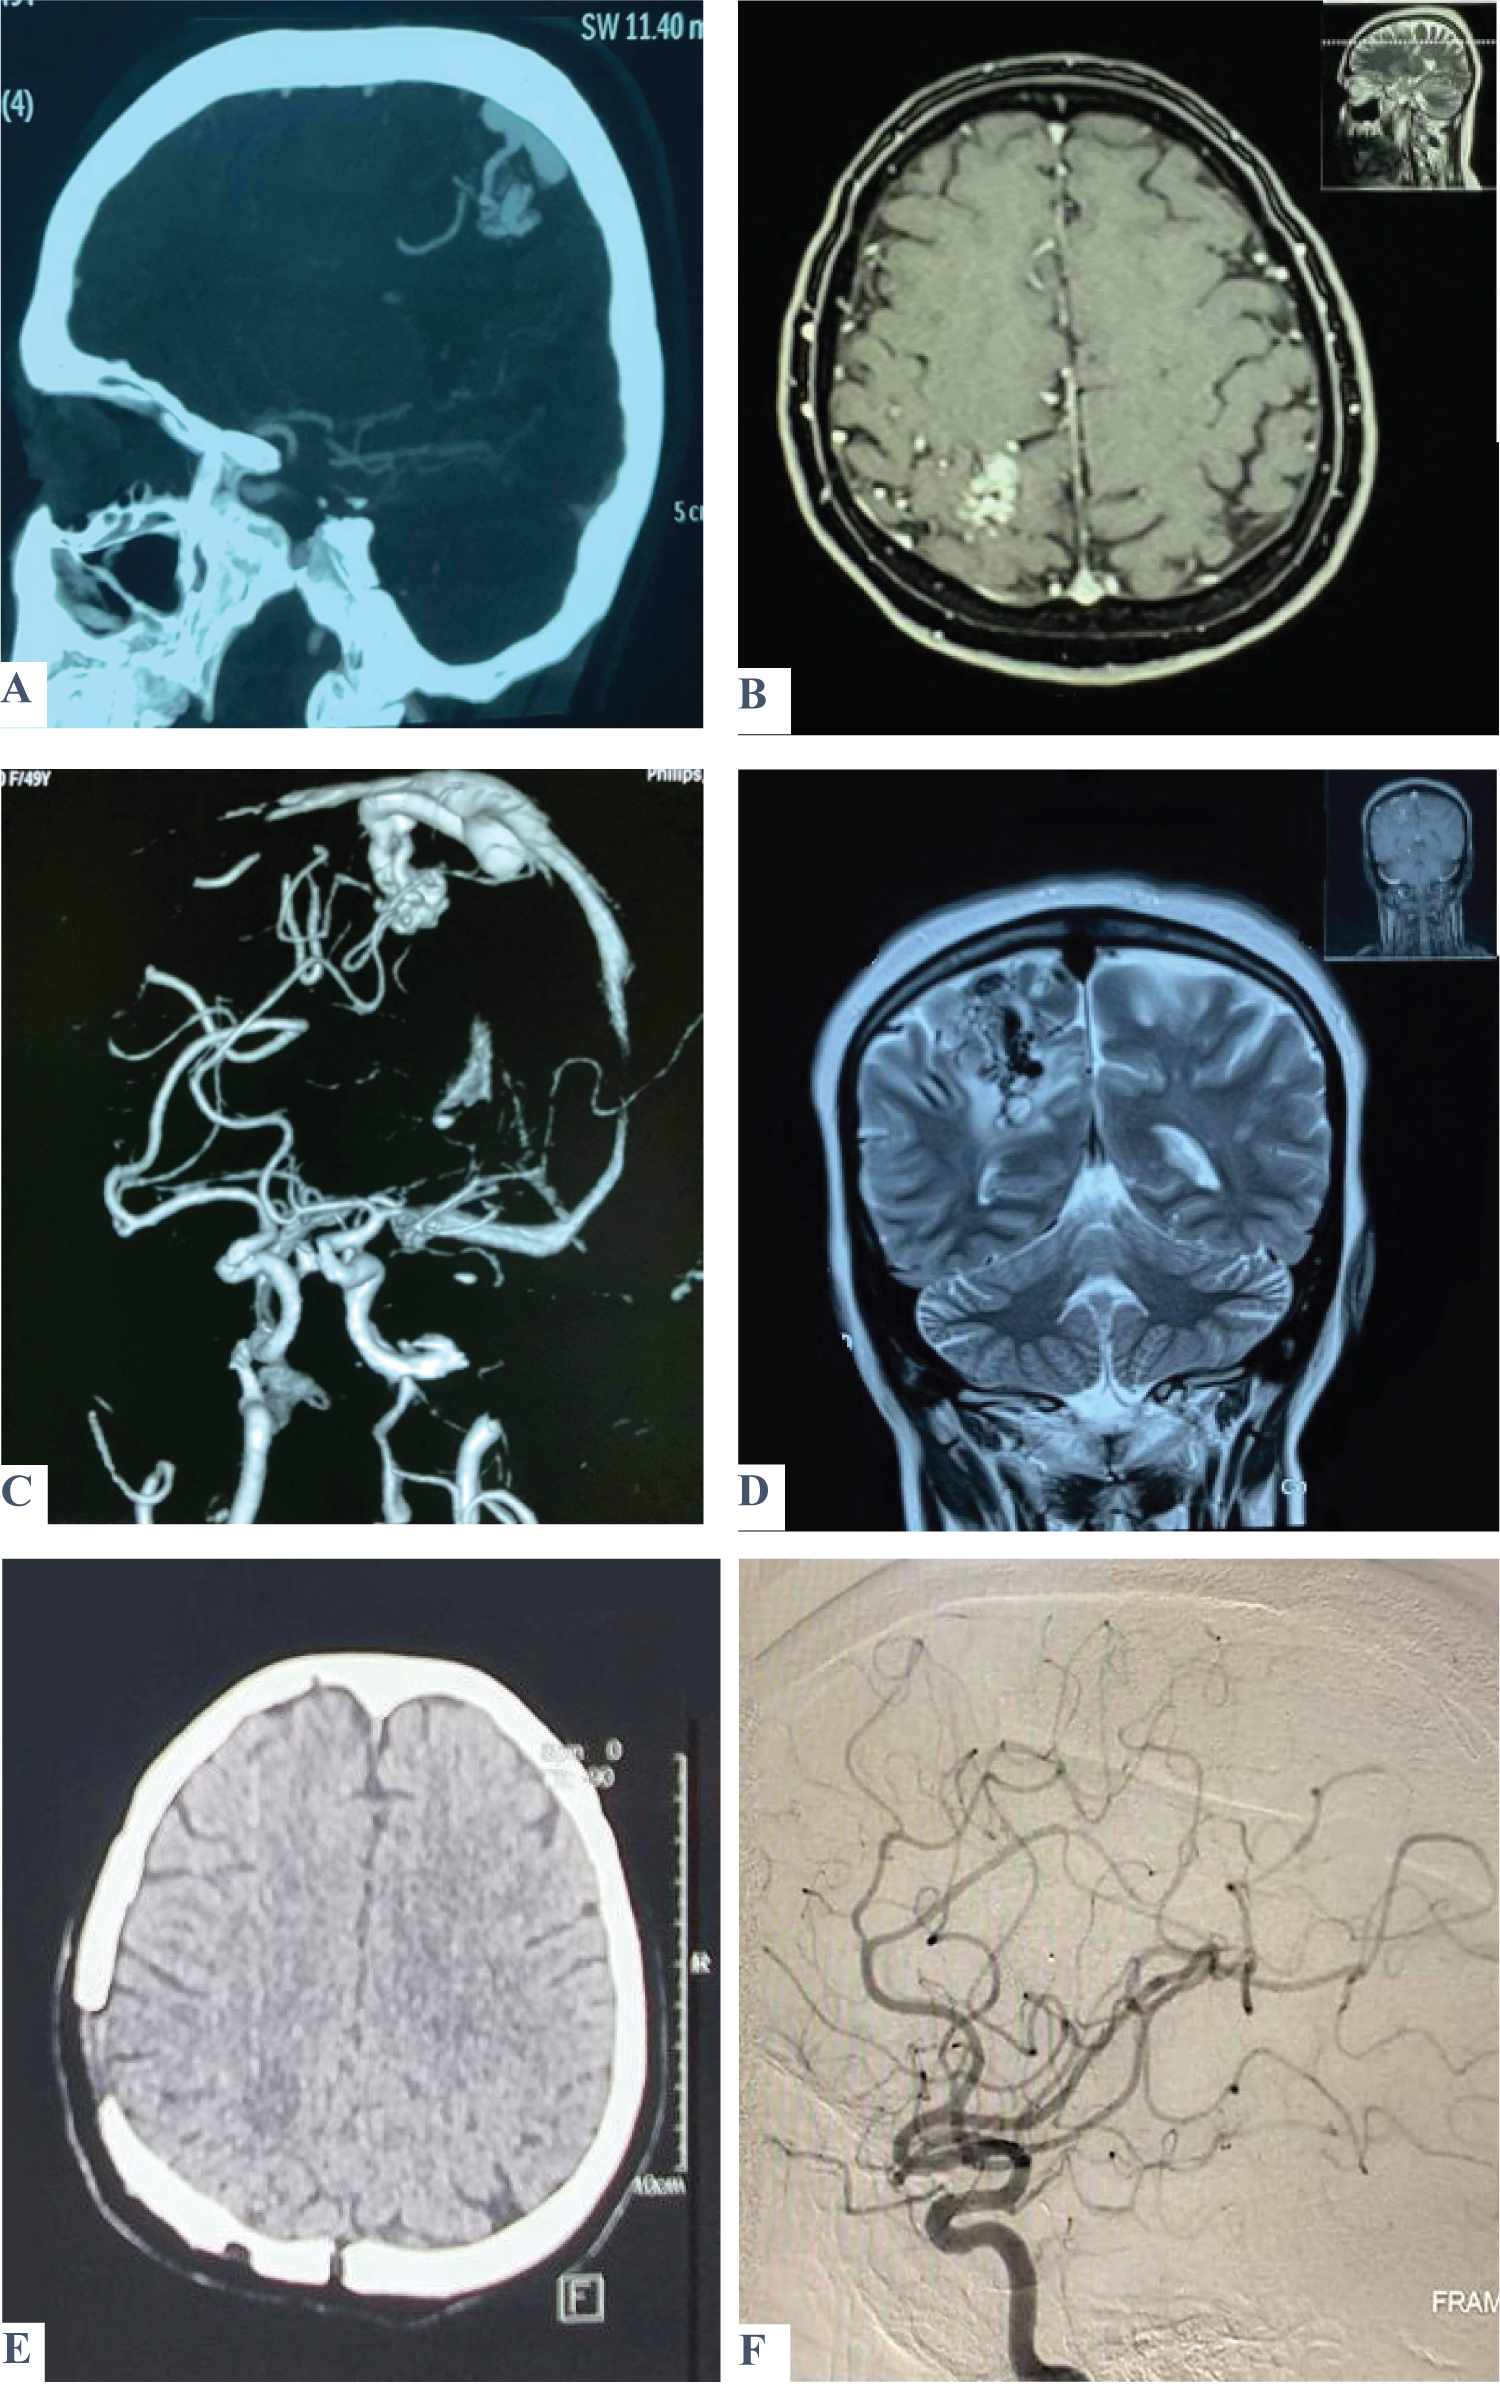

Figure 2: Shows a case of a 49-year-old female patient presented with three attacks of seizures. On admission, GCS was 15, with no fit, no vomiting, and no motor or sensory deficit. A brain CT scan (A) and MRI (B) show a heterogenous lesion within the posterior part of the Rt. parietal lobe involving the sensory area consistent with AVM, which was confirmed by MRA (C) and MRV (D). Post-operatively, GCS was 15 with no fit or vomiting. There was left-lower limb weakness but relieved on successive days. A postoperative brain CT scan and DSA revealed total excision of the lesion (E & F). View Figure 2